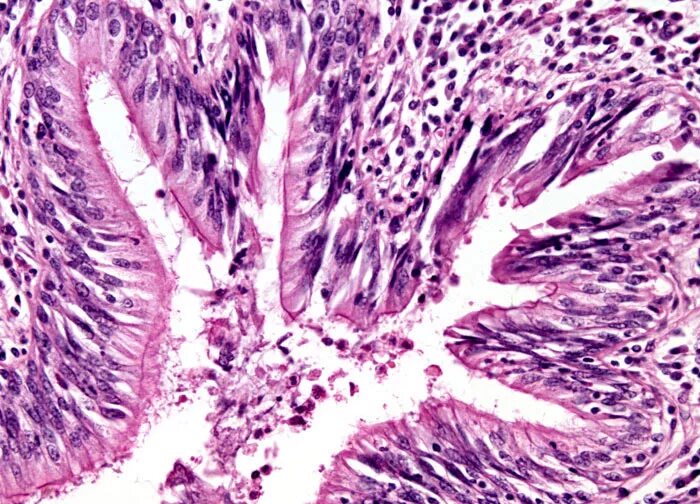

Серозный выпот